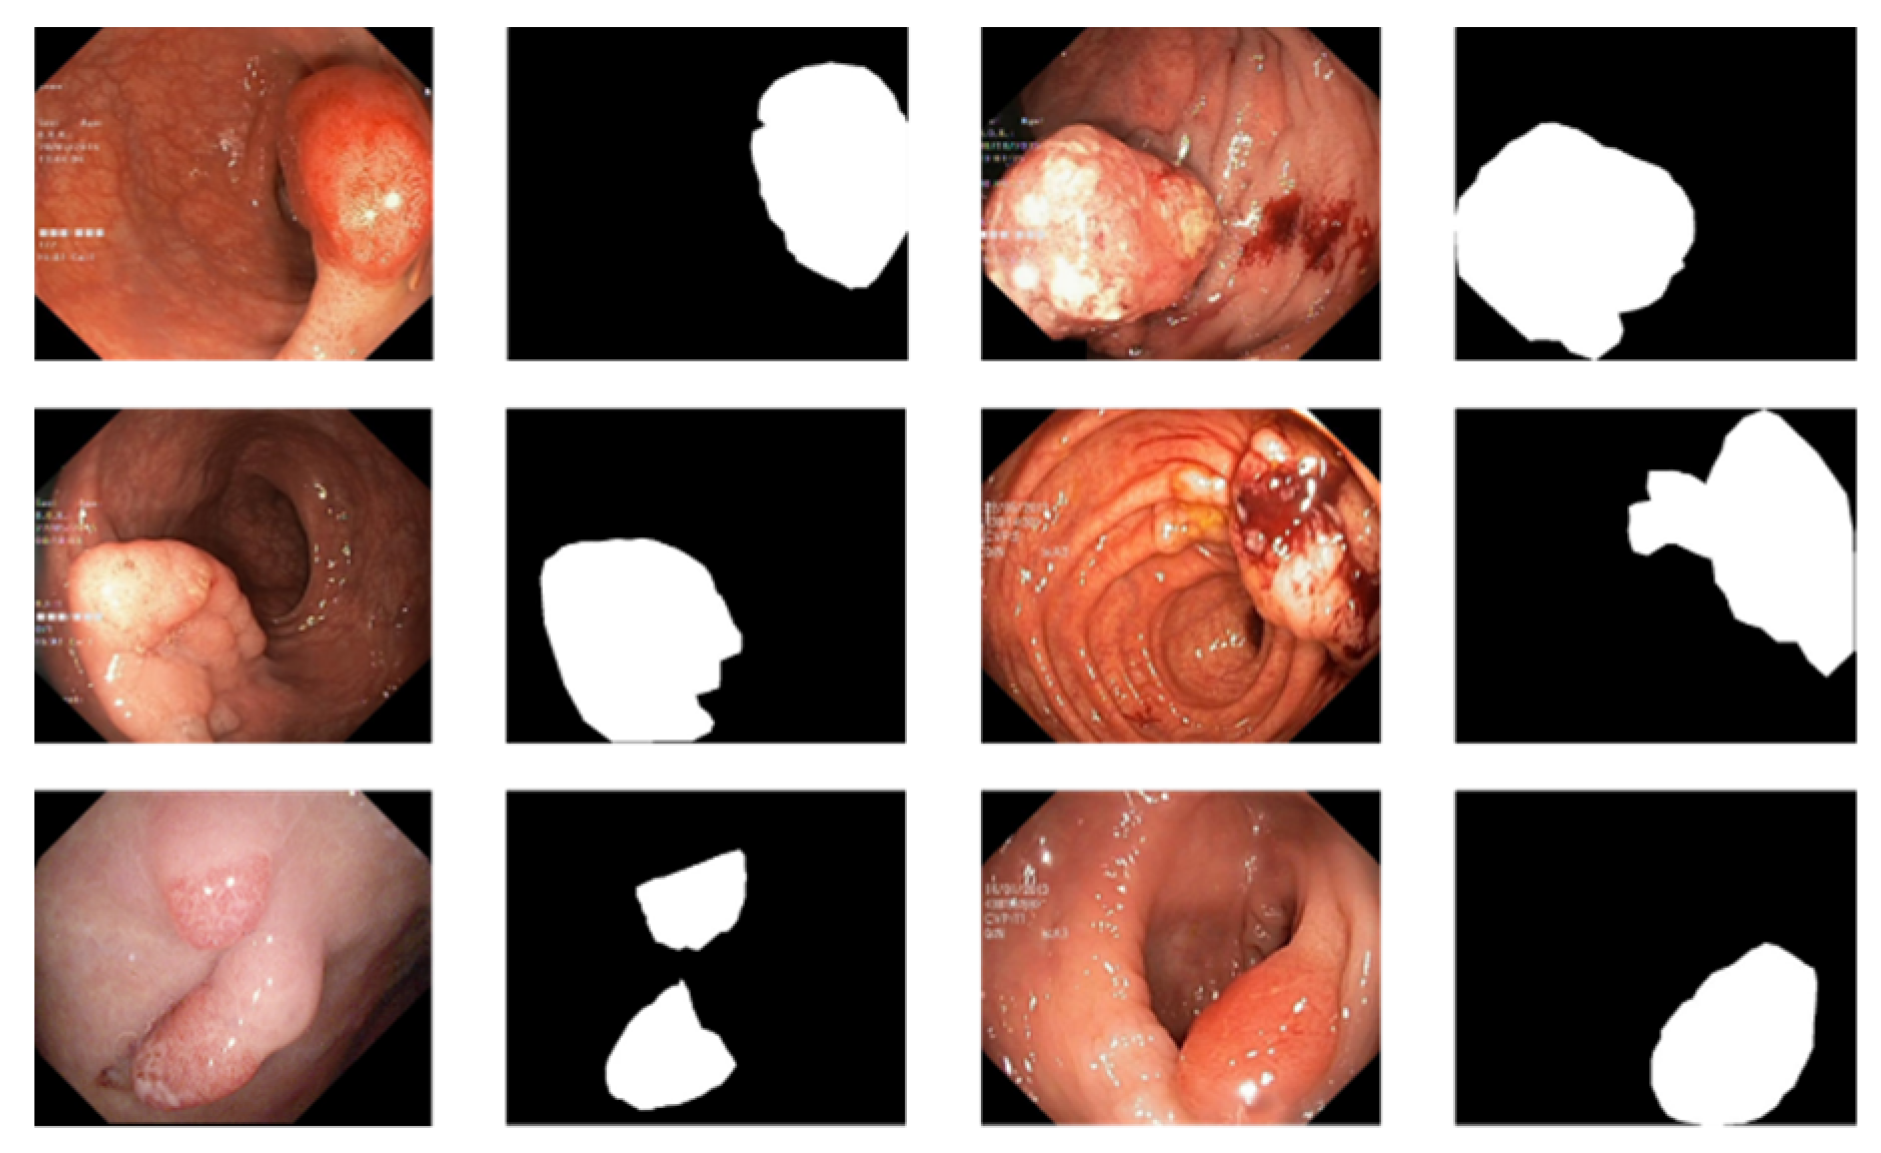

There are currently only a few public datasets of intestinal polyps available for model training and testing. Polyps exist in various shapes and colors as well as textures [11]. As shown in Figure 1, the minute difference between polyps and the normal ambient environment or partially diseased areas covering the feces is the main challenge in the detection of polyps. In this paper, we used the open datasets of Kvasir-SEG [12] and CVC-ClinicDB and performed relevant experiments

Figure 1.

An example of polyp pictures from the Kvasir-SEG dataset, together with their accompanying masks. The first and third columns show the original image; the second and fourth columns show the accompanying masks.

For the polyp image segmentation task, every pixel in the training image was labeled as either polyp or non-polyp. The evaluation of the PRAPNet was accomplished utilizing the Kvasir-SEG dataset and CVC-ClinicDB [17] dataset. The Kvasir-SEG dataset consists of 1000 polyp images and their corresponding mask maps annotated by specialist endoscopists from Oslo University Hospital, Norway. The CVC-ClinicDB dataset consists of 612 polyp images. Figure 1 shows example images from the Kvasir-SEG dataset and their corresponding templates. As the number of polyp pictures was too small, direct training would lead to overfitting. Thus, it was necessary to increase the number of polyp pictures in the training set; the number of Kvasir-SEG images was 11,000 and the number of CVC-ClinicDB images was 6732. Traditional data enhancement technology—namely, vertical flip, horizontal flip, 90 degrees clockwise rotation, translation, changing the image brightness, and Gaussian blur—was used to increase the training samples from the initial images. Of these images, 80% were randomly selected for the training, 10% were used for the validation, and 10% were used for the testing.